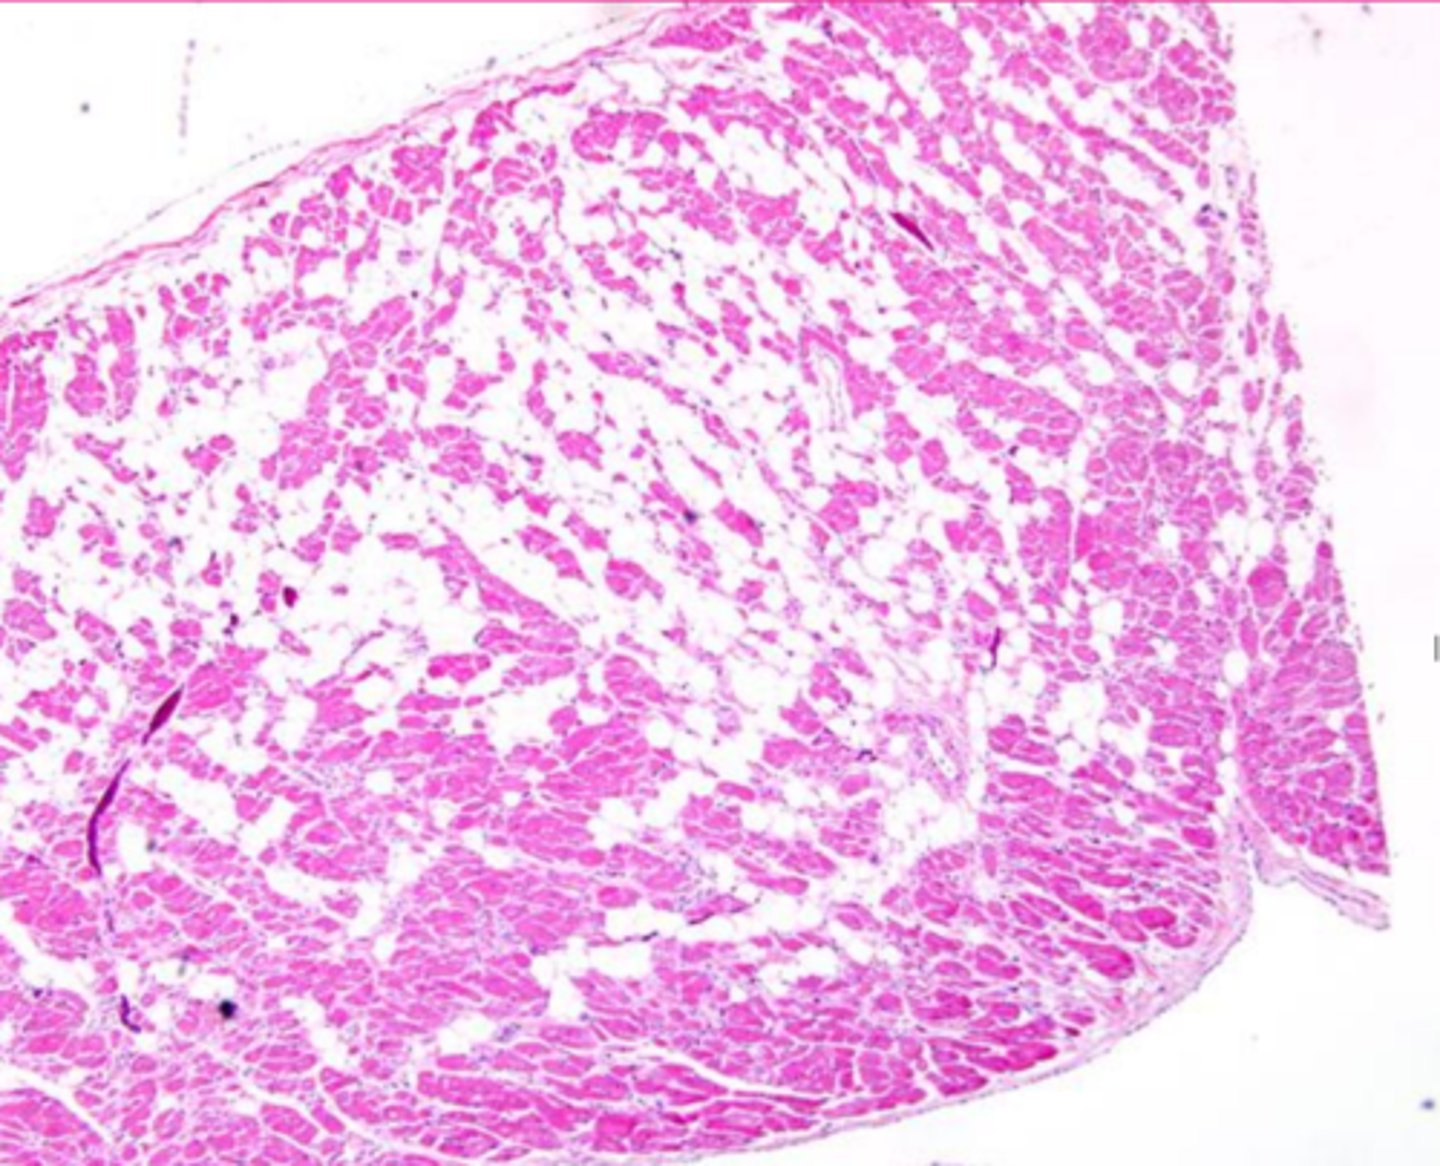

myocardial fibrosis

Describe this extracellular accumulation (heart muscle)

fatty infiltration

_______________: Increase in the number and/or volume of adipocytes in the interstitium of an organ or tissue due to obesity, cardio- or skeletal myopathies, or atrophied tissue

Describe the extracellular accumulation (this is a heart muscle)